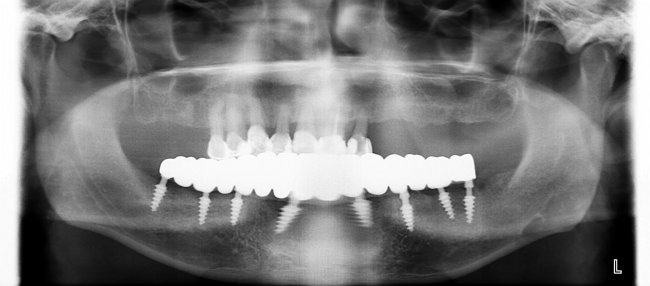

Хорошо себя зарекомендовали методы имплантации MiMi. Их используют в Европейском Стоматологическом центре Киева. Расскажем о некоторых из них. Например, MiMi при помощи пьезохирургии минимально травматичное. Пациент не чувствует боли, не происходит травматизация кости. Данный способ позволяет исключить риски и осложнения даже при наличии проблем с сердцем и сосудами.

Метод MiMi также рассматривают как альтернативу реконструкции кости. Имплантат вживляют без наращивания альвеолярного отростка. Применяют следующие технологии: pterygoid implant и установка конструкции для нижней челюсти без затрагивания каналов.